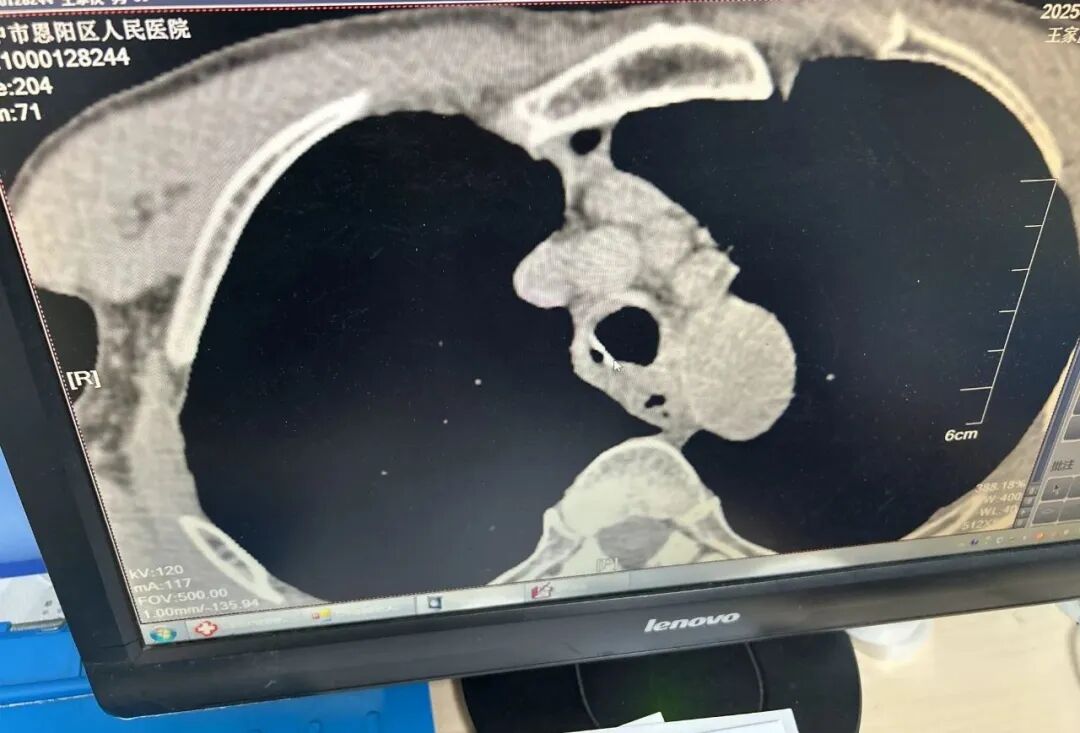

患者王某,入院前半月因吃鸡骨头时不慎卡住,此后便出现吞咽困难及疼痛症状且逐渐加重,伴咯血及呼吸困难,咽喉部疼痛不适,遂来区人民医院胸外科就诊,行胸部CT发现鸡骨尖锐端已穿透食管壁,导致食道穿孔,若不及时处理,可能引发脓胸、大出血甚至感染性休克。

面对复杂病情,医院迅速启动多学科协作机制。胸外科、消化内科、麻醉科、呼吸与危重症医学科家组成联合团队,结合患者影像学资料及全身状况展开深入讨论。最终决定采用胃镜联合纤支镜的“双镜联合”方案,通过胃镜定位异物,纤支镜辅助探查气管及纵隔情况,避免二次损伤。